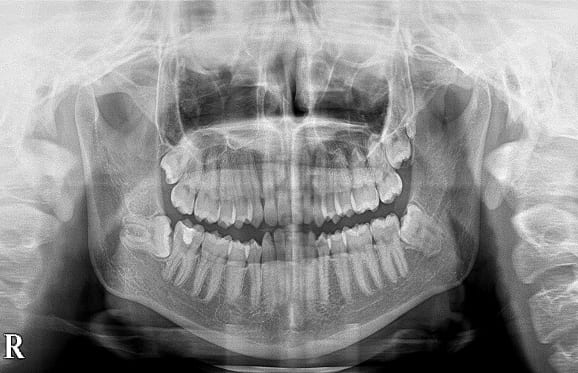

● C4を超え歯根までの虫歯を抜歯、親知らずを利用して歯並び全体を整えた症例

藤沢デンタルオフィスの虫歯や破折で抜歯後の部分矯正